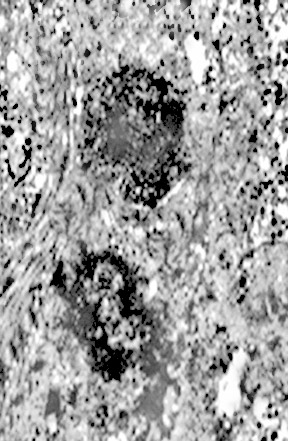

Fig.16  Fig.17